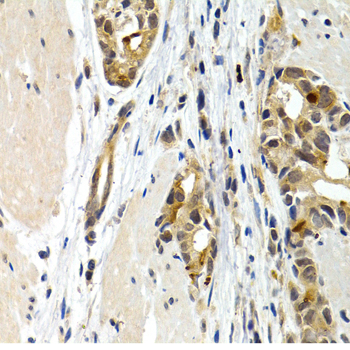

Immunohistochemistry of paraffin-embedded rat lung using IL9 at dilution of 1:200 (40x lens).

,

Immunohistochemistry of paraffin-embedded human colon cancer using IL9 at dilution of 1:200 (40x lens).

Immunohistochemistry of paraffin-embedded human stomach cancer using IL9 at dilution of 1:200 (40x lens).